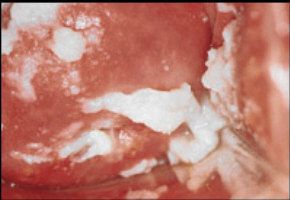

На складках влагалища заметен серый налет из клеток псевдомицелия. При острой форме встречаются отдельные группы налета, а при хронической они сливаются вместе. Влагалище отекает, развивается гиперемия. А после снятия налета слизистая кровоточит.

Поражение кожных покровов является очевидным и характерным признаком нарушения.

На пораженных участках образуются эрозии и белый налет. Генитальный кандидоз в зависимости от симптоматики может быть везикулезный и эритематозный. В первом случае наблюдается сильный отек, покраснение тканей и образование пузырьков. Эритематозный кандидоз сопровождается покраснением и эрозиями на месте развития грибков.

- гиперимированные пятна, с мокнущей поверхностью и сероватым налетом;

- очаги воспаления и эрозии;